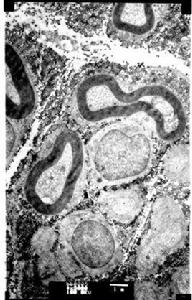

在光學顯微鏡下可見無定形物質沉澱於細胞之間,經剛果紅染色後在偏振光下呈綠色折光是澱粉樣物質的特徵。